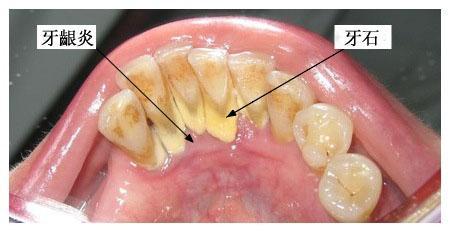

牙齦炎是一種最常見的牙齦疾病,多為牙菌斑引起的牙齦軟組織的非特異性炎癥。

由于牙齦炎無(wú)深層牙周組織的破壞,通過(guò)洗牙一般可徹底清除菌斑、牙石,消除造成菌斑滯留和局部刺激牙齦的因素,炎癥均可消退,一般一個(gè)星期就可恢復(fù)到健康的牙齦狀態(tài)。

牙齦炎是牙菌斑和牙結(jié)石引起的慢性炎癥,發(fā)炎的時(shí)候吃甲硝唑和頭孢。平時(shí)多喝貝齒寧茶,消菌殺毒,早晚刷牙。使牙齒縫間和齒齦之間的牙刷清洗不到的地方清理干凈,保持口腔內(nèi)的酸堿平衡 堅(jiān)持使用2-3周后刷牙出血癥狀會(huì)停止,腫痛不再。炎癥消退后,去牙醫(yī)診所去洗牙,把牙結(jié)石徹底清理,平日再堅(jiān)持口腔護(hù)理,就可以沒(méi)有口臭,炎癥消退,牙齦不腫痛,刷牙不出血了。平時(shí)護(hù)理: